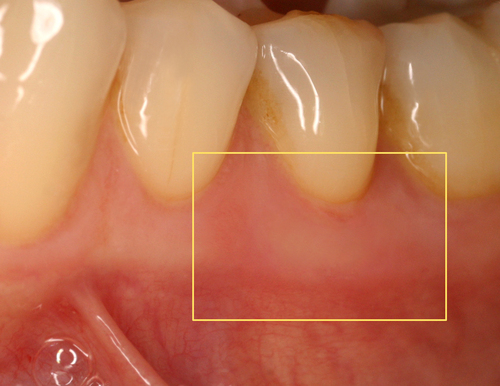

Par exemple, sur des aphtes douloureux (fig. 20) un rayonnement laser est rapproché progressivement jusqu’à une disparition quasi complète des sensibilités (fig. 21).

Fig.20 Présence de deux aphtes douloureux